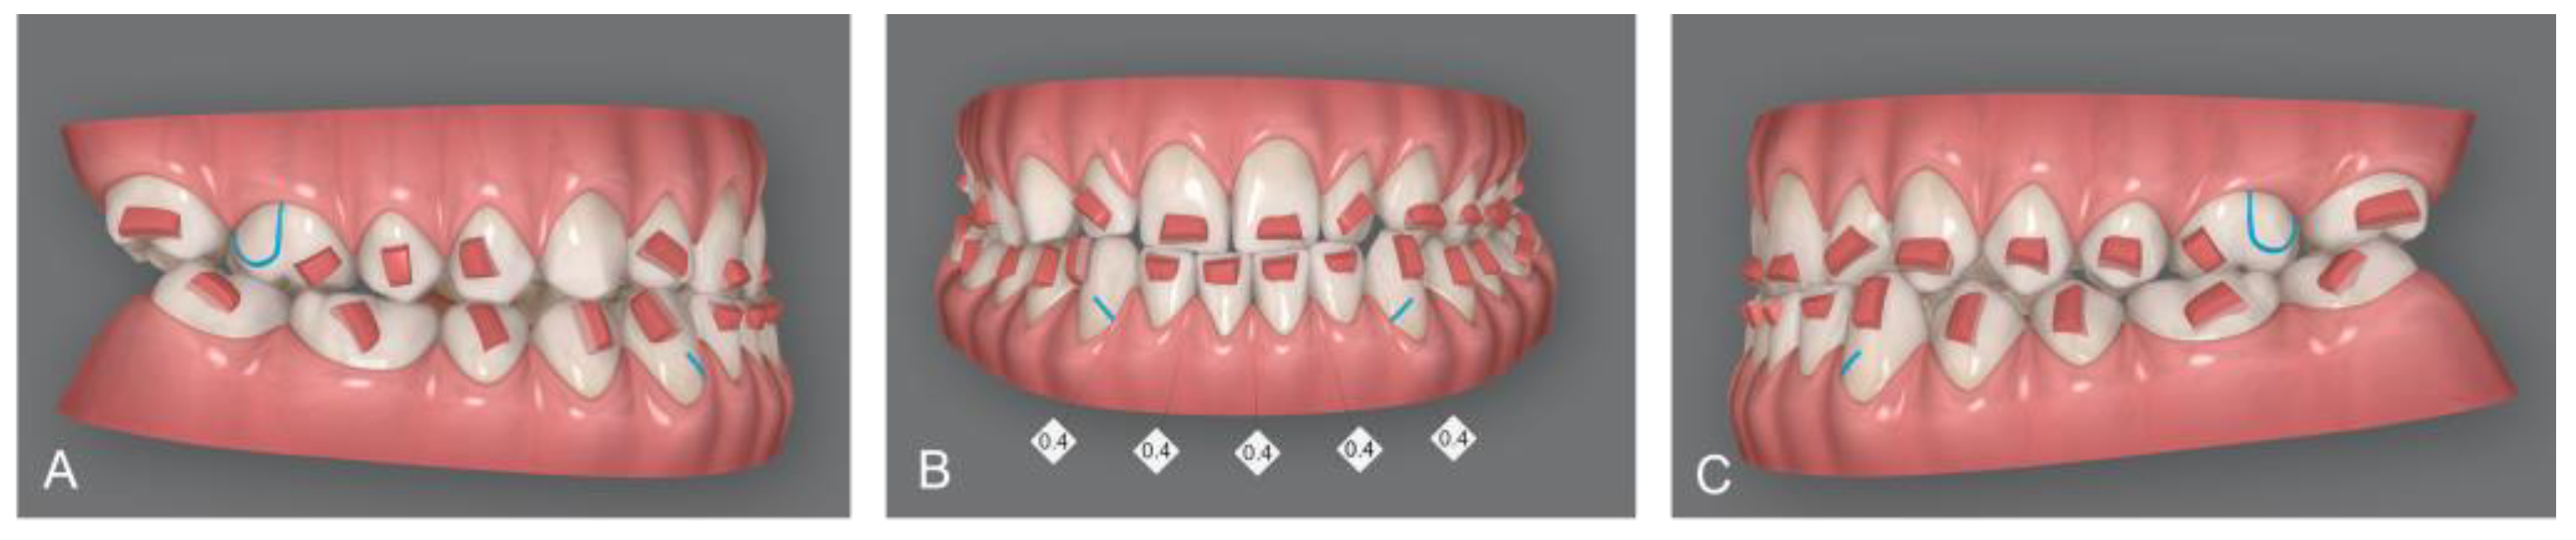

Upon delivery of the first transparent aligners, rectangular retention attachments were applied to the posterior teeth and rectangular attachments with gingival bevels on the lower anterior teeth to ensure maximum retention of the aligners. In addition, posterior attachments provided the proper retention and control of molars and premolars distal tipping, while retention attachments on lower canines and upper first molars prevented side effect movements with the application of class III intermaxillary elastics. Interproximal reduction (IPR) between lower incisors of 2 mm was planned (Figure 4). After third molar extraction, composite attachments and metal buttons for elastic support were bonded. Orthodontic elastics plus clear aligners were delivered to the patient [22].

Figure 4. Invisalign® software display of attachments, programmed IPR and cuts for elastic: Right lateral vision of virtual setup (A); Frontal vision of virtual setup; IPR of 0.4 mm from canine to canine was planned (B); Left lateral vision of virtual setup (C).